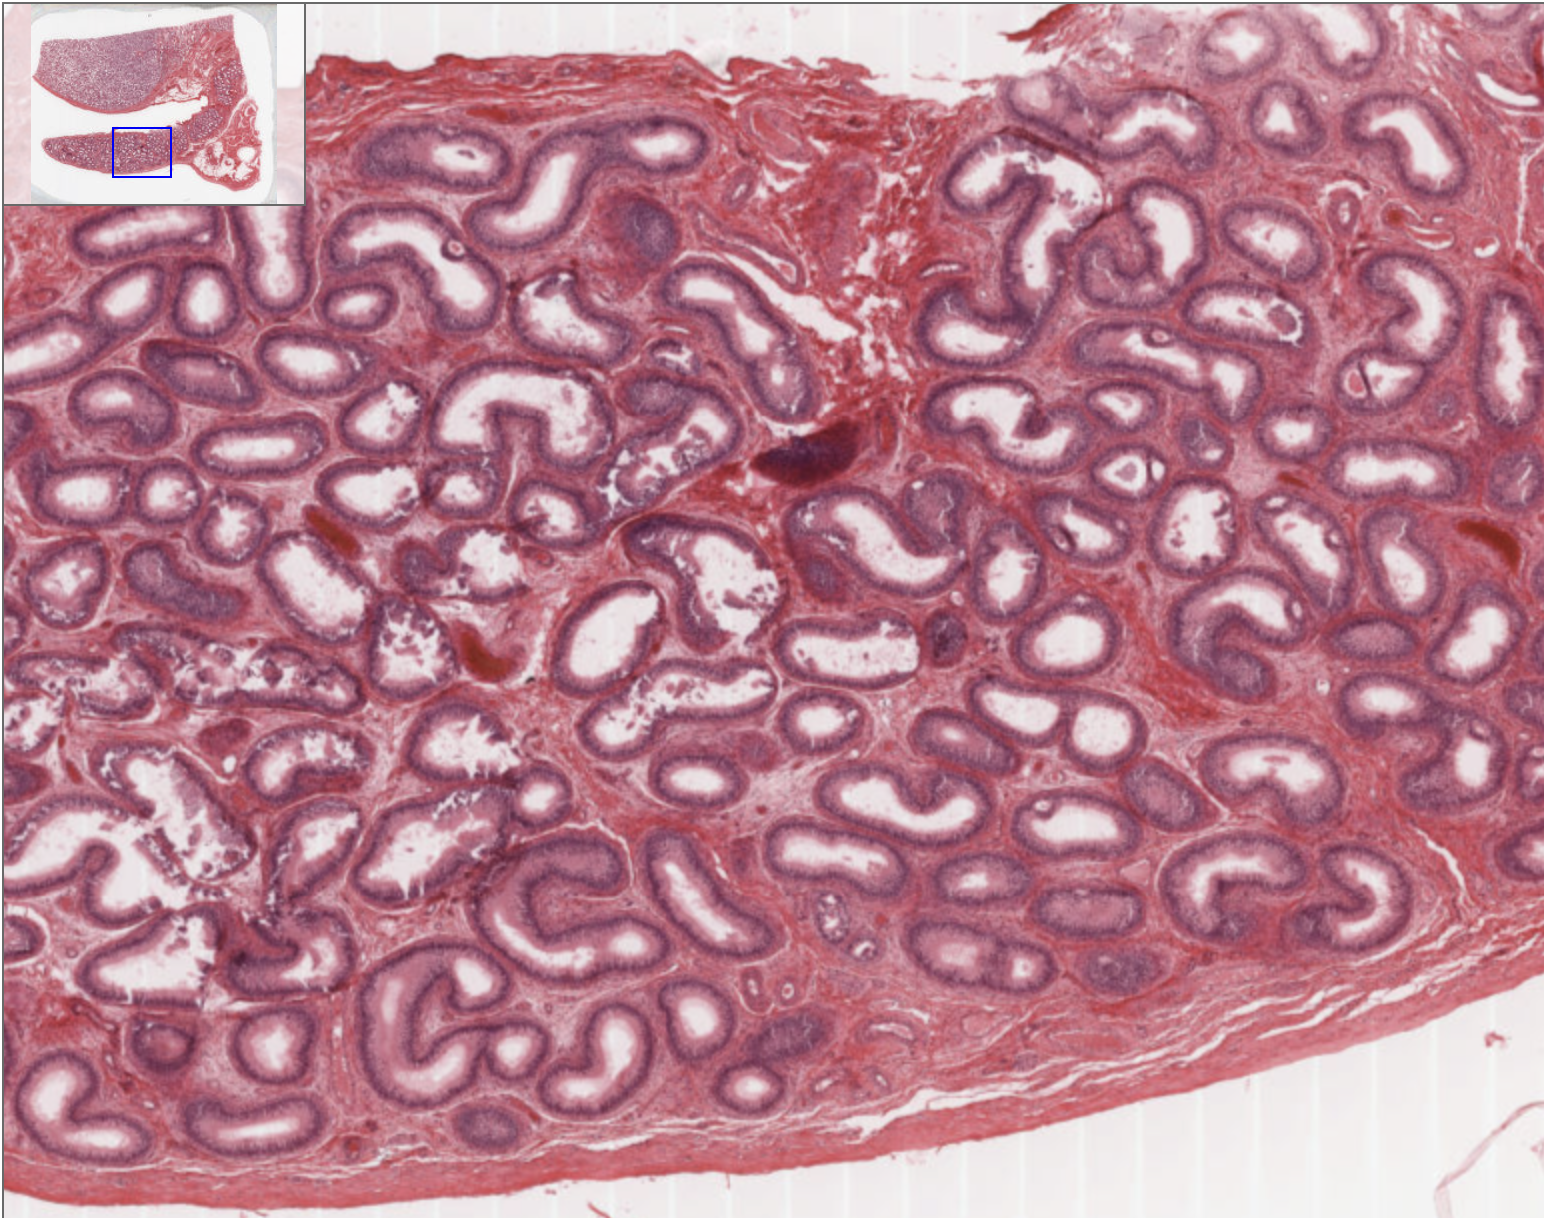

How can you identify a testis on a slide?